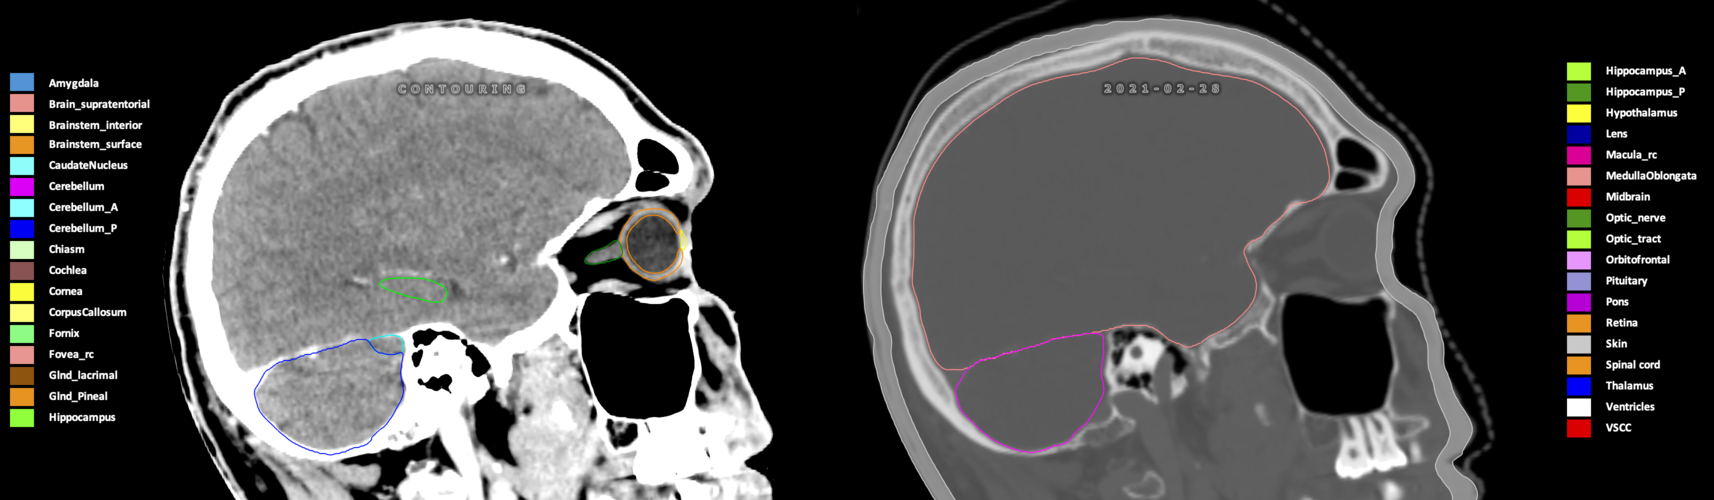

Included are all OARs known to be relevant for radiation-induced toxicity in neuro-oncology: brain, brainstem (midbrain, pons, medulla oblongata), chiasm, cerebellum (anterior & posterior), cochlea, cornea, hippocampus (anterior & posterior), hypothalamus, lens, lacrimal gland, optic nerve, pituitary, skin, and vestibular & semicircular canals. To further facilitate research on cognition, vision and radiological changes after irradiation of the brain, potential clinically-relevant OARs are included: amygdala, caudate nucleus, cerebellum (anterior & posterior), corpus callosum, fornix, macula, optic tract, orbitofrontal cortex, periventricular space (PVS), pineal gland, and thalamus.

Three-dimensional delineation of the 25 consensus OARs for neuro-oncology are shown on CT (WW/WL 120/40, 3000/600), 3T MR images, (T1Gd, T2FLAIR 1mm) and 7T MR (MP2RAGE 0.7 mm). All are presented in transversal, sagittal and coronal view.